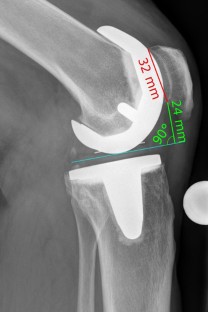

Fig. 1